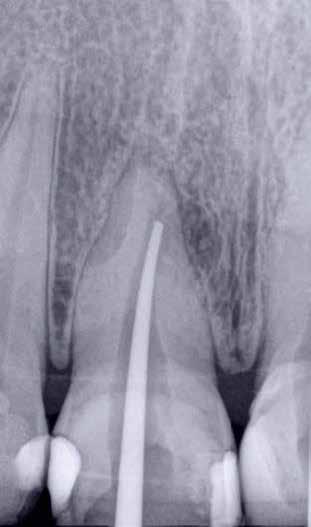

ai felvételek segítségével viszonylag jól el lehet különíteni a külső rezopció okozta ártalmaktól. A belső rezorpciótól szenvedő fogak esetében a radiológiai felvételek excentrikus irányból történő elkészítése során a rezorptív lézió a fog gyökércsatornájával egy irányba mozdul el a felvételen, míg külső rezorpció esetében le fog vetülni a gyökércsatornáról. 1999 márciusában egy 47 éves hölgy páciens arcduzzanattal kereste fel a rendelőnket. Klinikai vizsgálat során a jobb felső nagymetszőfog (11) kopogtatásra való érzékenységét tapasztaltuk. A felső front régióról készült periapikális felvételeken a frontfogakban lévő nagy kiterjedésű III. és IV. osztályú restaurátumokat észleltünk. Az 11-es fog gyökércsúcsa körül periapikális felritkulás volt látható. A 21-es fognál a gyökér középső harmadában belső rezorpciót észleltünk (13. ábra). A páciens kérdésünkre elmondta, hogy a bal felső nagymetszője közel 35 évvel ezelőtt traumás sérülést szenvedett. Mivel abban az időben CBCT-felvételek készítése nem volt számunkra elérhető, így a klinikai adatok alapján azt feltételeztük, hogy a rezorptív lézió bukkális irányba perforálta a gyökércsatorna falát, majd ezt követően az ezt a területet fedő bukkális csontállományt is destruálta.

A frontrégióban végzett szenzibilitás vizsgálat is megerősítette a 11 fogban a fogbélelhalás diagnózisát. Az 11-es fog endodonciai kezelése során a gyökércsatorna biokemo-mechanikai megmunkálását követően a gyökércsatornát meleg vertikális kondenzációs technikával zártuk. A bal felső nagymetsző esetében a gyökércsatorna megmunkálását a rezorpciós üreg koronális határáig végeztük, majd a megmunkált csatornaszakaszt fehér MTA-val töltöttük fel (14. ábra). Amennyiben ennek a fognak a kezelését ma kellene elvégezni, akkor az EndoSequence BC puttyt (Brasseler) használnánk a gyökértömés elkészítésére. Ezenkívül azt is megemlítenénk, hogy manapság egyre gyakrabban próbál-

13. ábra: A periapikális felvételen jól lekövethető a 11-es fog gyökércsúcsa körül látható radiolucens terület körvonala. A 21-es fog gyökerének középső harmadában pedig belső rezorpció jelenlétére utaló jelek észlelhetőek. A rezorptív lézió frontális és laterális irányban is áttörte a csontos falakat, amely következtében a gyökeret körülvevő csontállomány is károsodott. – 14. ábra: A posztoperatív felvételen jól megfigyelhető a 11-es fogba helyezett gyökértömés. A 21-es fog ellátása során a gyökércsatorna megmunkálását csak a rezorptív defektus koronális határáig végeztük. A gyökércsatorna zárására fehér MTA-t alkalmaztunk. – 15. ábra: A 11-es fog gyökércsúcsa körül látható felritkulás teljesen eltűnt. A rezorptív defektus mérete csökkent, valamint a rezorpciós üreg csontosodására utaló jelek is megfigyelhetőek. – 16. ábra: A saggitalis irányú CBCT-metszeten jól látható, hogy a 21-es fogat ép és jól megtartott bukkális kortikális csont fedi. A rezorpciós üreg mérete jelentősen csökkent, valamint az üreg kalcifikálódott anyaggal való telődése is megfigyelhető volt.

koznak a rezorptív léziók injektálható PRF-fel történő kezelésével. Az eddigi eredmények alapján ezzel az eljárással rendkívül kedvező hosszú távú eredményeket lehet elérni. A 21 évvel később készített kontrollfelvételeken látható, hogy az 11-es fog gyökércsúcsánál látható periapikális lézió teljesen eltűnt, valamint a rezorptív lézió mérete is jelentősen csökkent (15–16. ábra)